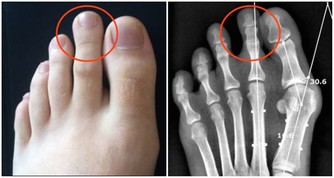

一種是大汗腺(頂漿腺),主要分布在腋下、陰部、肛門、乳頭和肚臍等周圍,

會分泌黏稠乳黃色的液體,與體溫調節無關,但與個人體味有關。

當頂漿腺的分泌液被腋窩皮膚表面的細菌分解後,會產生一股惡臭的味道,即所謂的狐臭。